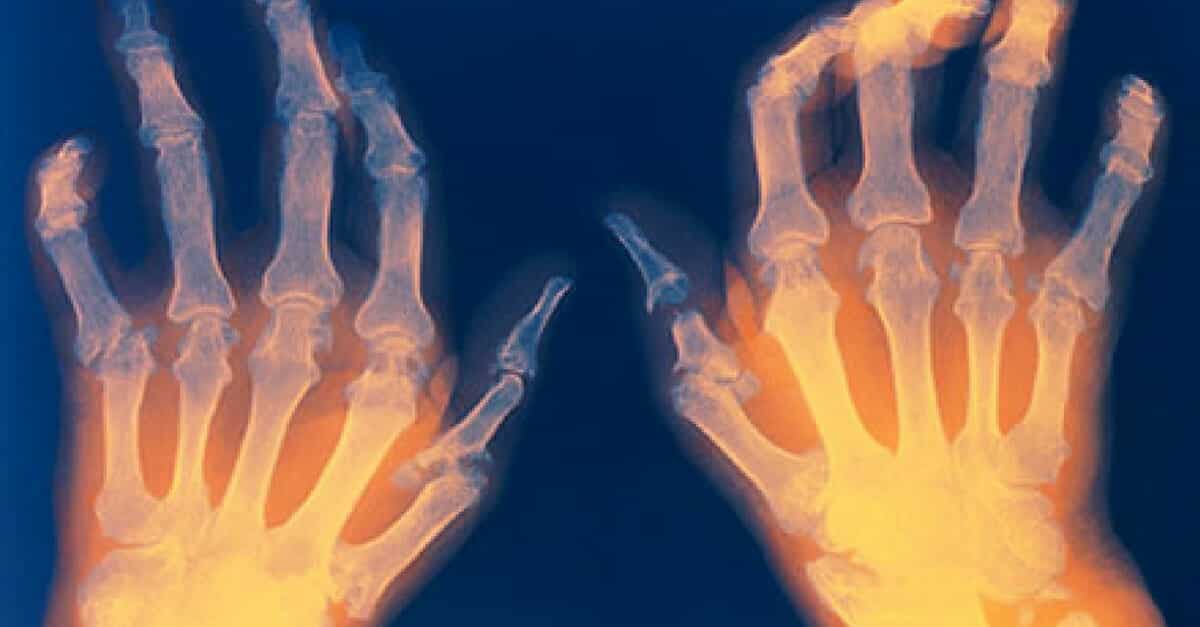

Los dolores en las articulaciones tienen múltiples causas, la más común de las cuales es la artritis reumatoide. Esta enfermedad afecta hasta el 1% de la población brasileña, por ejemplo.

Entre los síntomas de la artritis reumatoide se encuentran:

- Dolores en las articulaciones

- Inflamaciones en las articulaciones

Debes estar atento a la artritis reumatoide, porque esta es una enfermedad de evolución continua. Esto quiere decir que puede empeorar, causando más dolores y empeorando los síntomas. Hay casos en que las articulaciones se ponen rígidas y pueden afectar completamente el movimiento.